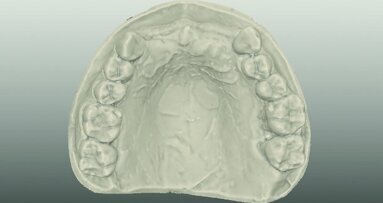

After extraction of tooth #21, the apical granulation tissue was excochleated through a semilunar incision (Fig. 3). A two-stage procedure was performed to prevent failure of osseointegration of the ceramic implant and to preserve the soft-tissue structures (papillae and attached gingiva). A claspless prosthesis made from Valplast (Valplast International) served as a temporary restoration. The implant site in region #21 was uncovered after five months (Fig. 4). A two-piece ceramic implant (diameter: 4.2 mm; length: 12.0 mm) was then inserted (Figs. 5a & b). The guidelines for implant placement in the aesthetic zone and the drilling procedure specified by the manufacturer were observed.13, 14 Both vertical and transverse insertion depth are decisive for prosthetic success. The implant can be placed between 1.6 mm and 0.6 mm supracrestally because of a special thermal etching procedure in the collar region; the insertion depth is determined by the gingival height and the existing bone of the adjacent teeth. The implant positioning should be approximately 2–3 mm subgingivally because the abutments are added 1 mm above implant shoulder level. Transversal bone augmentation was performed with a mixture of autogenous bone chips (retrieved from the retromolar mandible), xenograft (Geistlich Bio-Oss, Geistlich Biomaterials) and guided bone regeneration (Jason membrane, botiss biomaterials; Figs. 6a & b). The exposure was performed after four months using a PEEK gingiva former (Fig. 7).